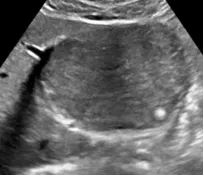

肝囊肿

● 肝内单个或多个无回声区。

● 边界清,形态一般规整,少数欠规整。

● 内透声好,少数可见分隔。

● 后方回声增强。